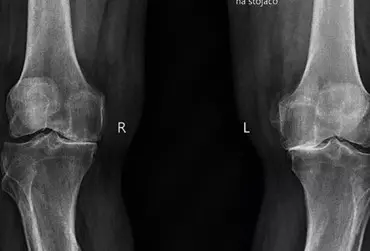

Endoprotezoplastyka stawu kolanowego — kompleksowa fizjoterapia szpitalna

Zwiększona aktywność fizyczna zarówno amatorska, jak i zawodowa może powodować wiele urazów, które w perspektywie czasu przyczyniają się do powstania rozmaitych chorób. Przeważnie choroba zwyrodnieniowa stawów przyczynia się do zmniejszenia ruchomości stawowej skutkującej różnorodnymi niedogodnościami. Schorzenie to stanowi również poważny problem nie tylko medyczny, ale również ekonomiczny. Zważywszy na fakt, iż jesteśmy społeczeństwem starzejącym się, z pewnością problem z roku na rok będzie się pogłębiał.

Usprawnianie chorych z chorobą zwyrodnieniową stawów kolanowych

Kompleksowa aktywność fizyczna zarówno amatorska, jak i zawodowa jest dominującą częścią naszego życia. Odpowiednio wykonywana zapewnia prawidłowy oraz harmonijny rozwój całego organizmu. Ruch pod różnymi postaciami wpływa pozytywnie na wiele narządów i układów. Pod wpływem różnorodnych ćwiczeń stawy, zwłaszcza narządu ruchu, pozostają we właściwej kondycji. Staw kolanowy jest narażony na liczne urazy oraz choroby. Zwłaszcza choroba zwyrodnieniowa upośledza jego odpowiednie funkcjonowanie. W perspektywie czasu doprowadza w dużej mierze do uszkodzenia określonych struktur, np. chrząstki stawowej.